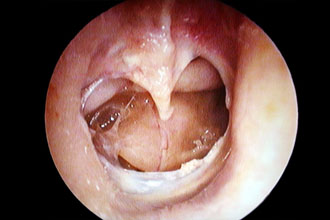

- Миринготомия — процедура, при которой в барабанную полость вводятся тонкие трубки для отведения серозного содержимого из среднего уха. В процессе заживления трубки естественным образом вытесняются из слухового прохода до полного удаления.